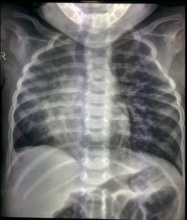

Repair of Scimitar Syndrome and Closure of Large Malaligned Subaortic Ventricular Septal Defect [1]

Surgical management of scimitar syndrome with hypoplasia of the right lung and additional systemic arterial supply to the right lung, with an associated ventricular septal defect (VSD), in a six-month-old infant is challenging. Various treatment options have been described. The authors demonstrate a simple, reproducible operative technique with good mid-term results.